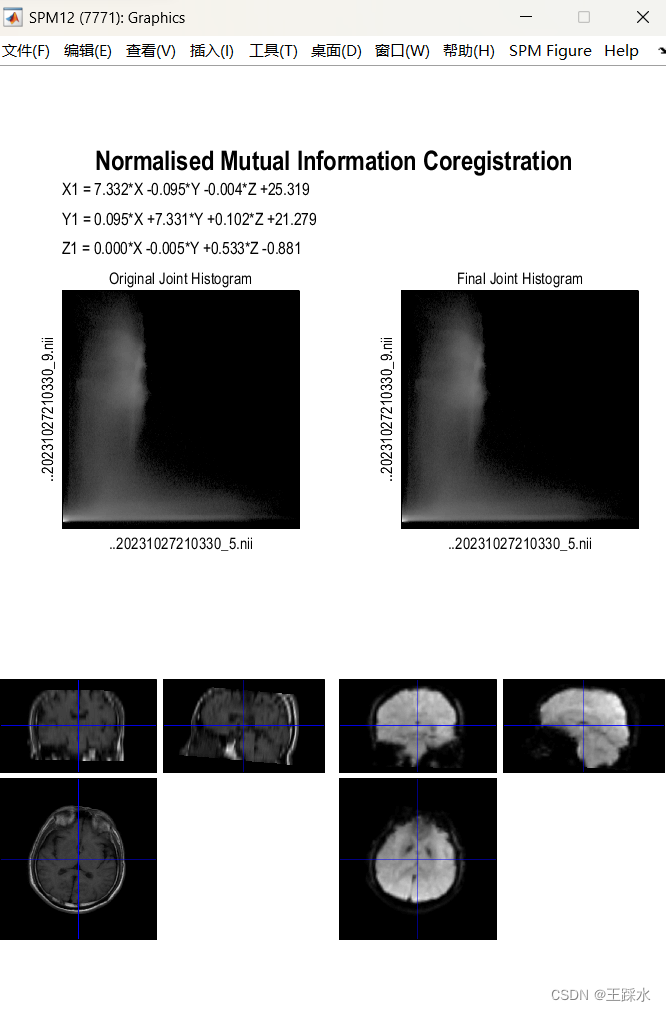

3、空间配准

这部分就是要把大头、小头都配准到一个标准的头中!我用的是:功能像向结构像看齐、结构像向标准空间看齐。

coregister 是功能像配准到结构像(选择estimate就可以,只需要输出那个数值,不需要生成新的图像);normalise 是结构像配准到标准空间。

(我的功能像配准到结构像,不知道为啥,拖动不了那个蓝色的十字标)

空间配准完成!展示的是一个标准空间还有一个是功能像生成的第一帧